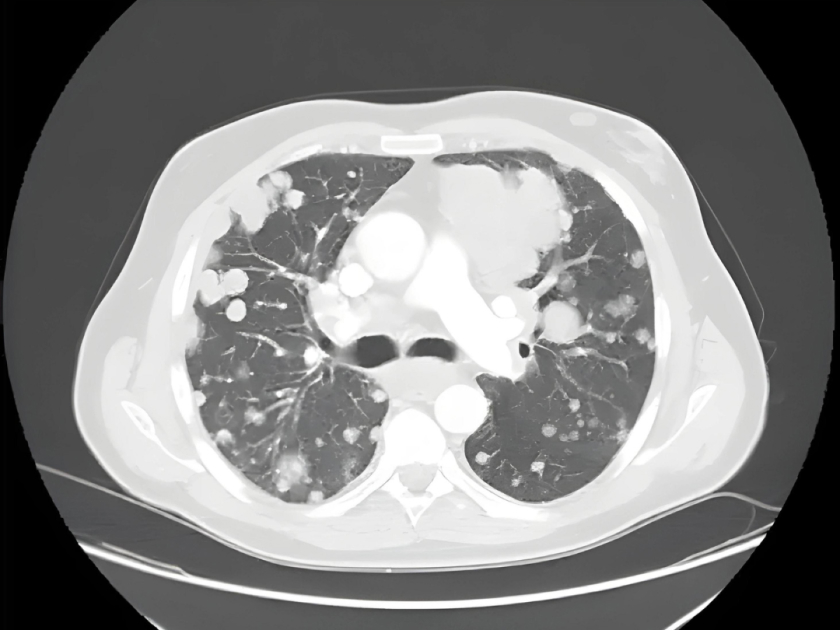

Metástasis pulmonares

Las metástasis pulmonares son tumores cancerosos que comienzan en otra parte del cuerpo y se diseminan a los pulmones.